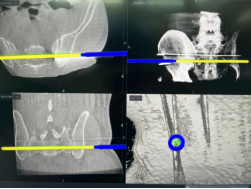

治疗前,孟文凯院长团队会用O臂智能导航的3D立体影像系统,对患者的关节进行360度快速三维扫描,几十秒就能生成CT级的高清影像。通过这些影像,医生能清楚看到关节里滑膜增生、软骨损伤、骨质融合的具体情况,提前规划好最佳的微创路径或手术方案。技术人员再根据这个方案,定制适配的手术器械或金属假体,确保和患者的骨骼完美贴合,从根源上避免传统手术的过度损伤、假体错位,以及术后疼痛、脱位等并发症。

更关键的是,团队还能提前演练整个治疗过程,做到心中有数。手术中,医生通过微创小切口操作,避开神经和血管,精准清理病变组织或植入假体。每一步操作都有量化的可视化指引,就像有“GPS导航”全程护航,哪怕出现0.1毫米以上的偏差,系统都会立即预警并引导调整,真正实现“零误差”施治。

以前的类风湿微创治疗或手术,虽然能看到关节的大致结构,但对关节内部骨质、滑膜的细微病变,还是看不清。而O臂智能导航系统的超高清可视功能,就像一双“透视眼”——20倍动态放大视野,能清晰捕捉到毫米级的骨质侵蚀、细小的炎性组织,以及深层隐藏的病灶,帮医生精准区分健康组织和病变组织,彻底清理病灶,让治疗更精准、效果更持久。